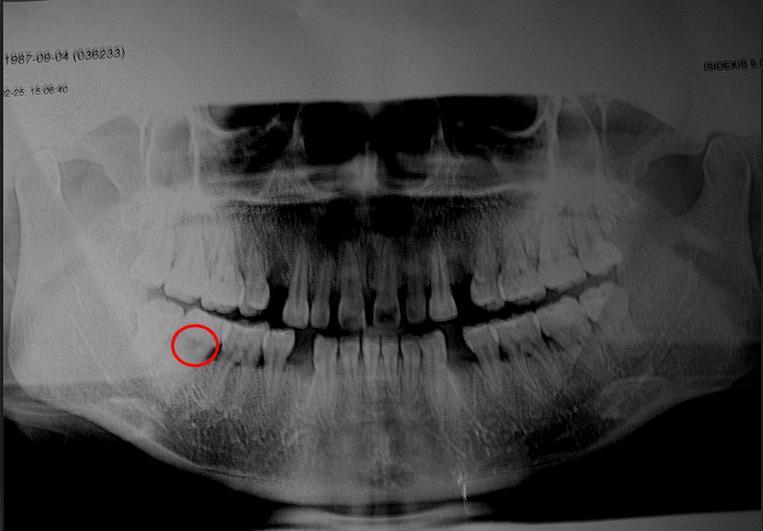

口腔科的专家看过来,看看能不能正畸(附上x片)